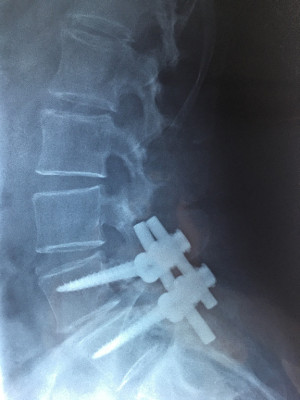

Cirugía endoscópica de columna e instrumentación

Envíado por Dr. Hugo Enrique Castro Cordero